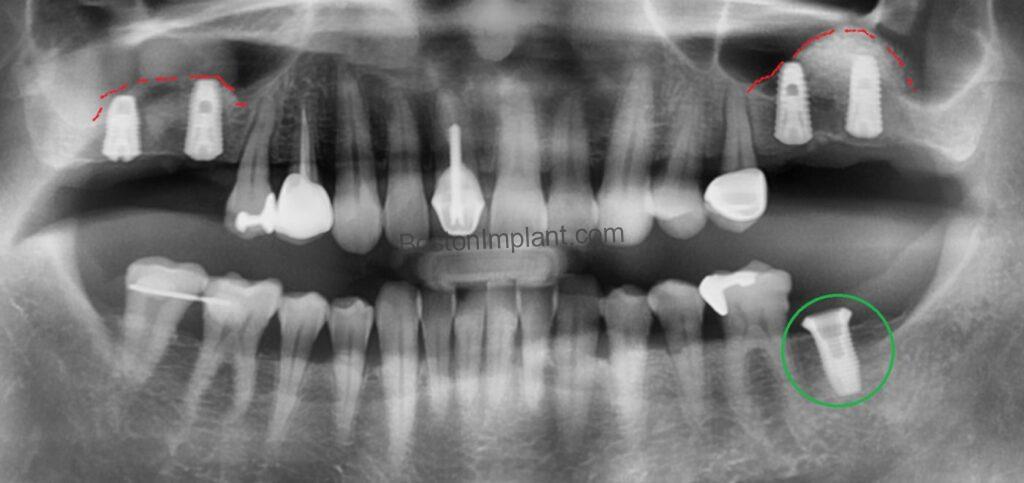

The surgical procedures were completed successfully. The sinus grafts were placed in both molar areas (red lines). Notably, you can see the lower right back implant (green circle) has different shape than other. It is a tissue-level implant, chosen for its stability as a solitary implant. (For details on implant types, please see this post.)

Finally, regarding the lower left tooth (green circle), we opted for a conservative reshaping, which proved successful, avoiding the need for more extensive treatment.